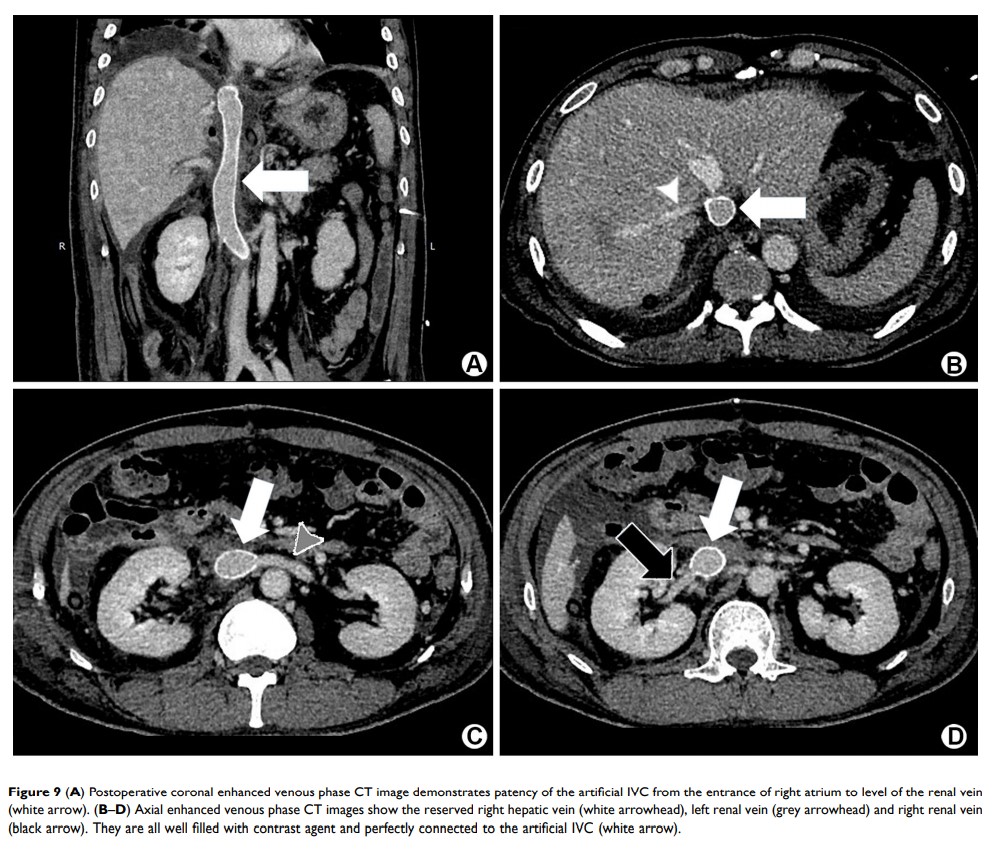

一个巨大下腔静脉平滑肌肉瘤病例:通过 Gadobutrol 增强 MRI 进行精准的术前评估